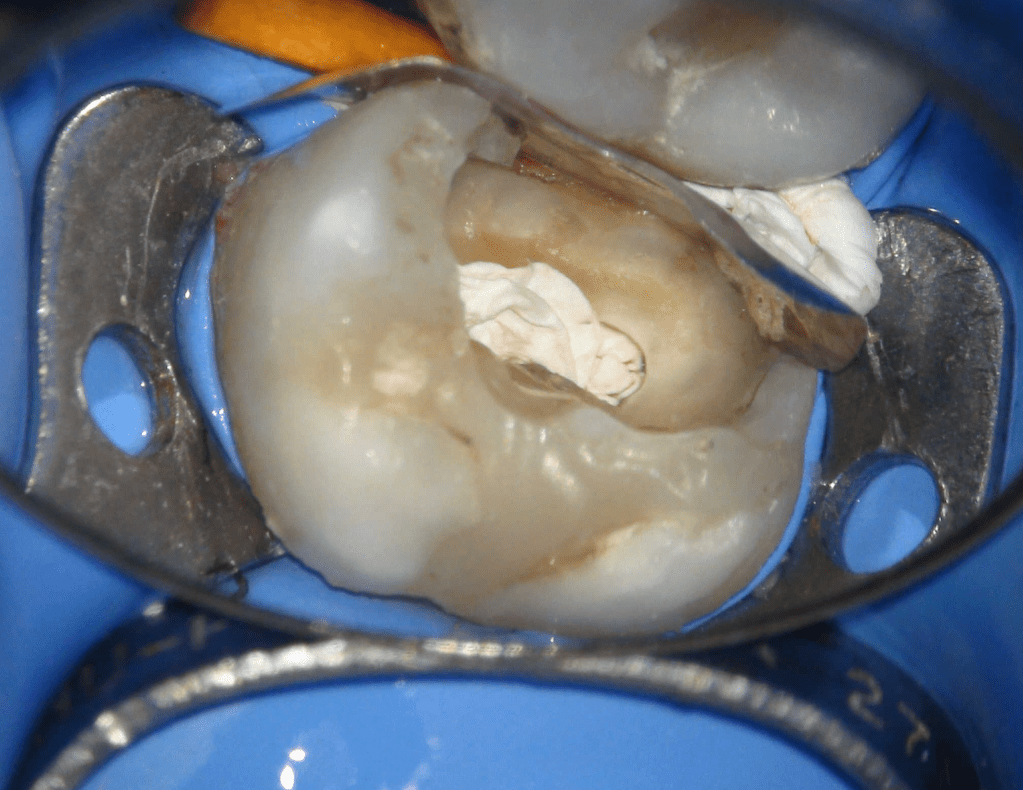

Reco pared vesticular